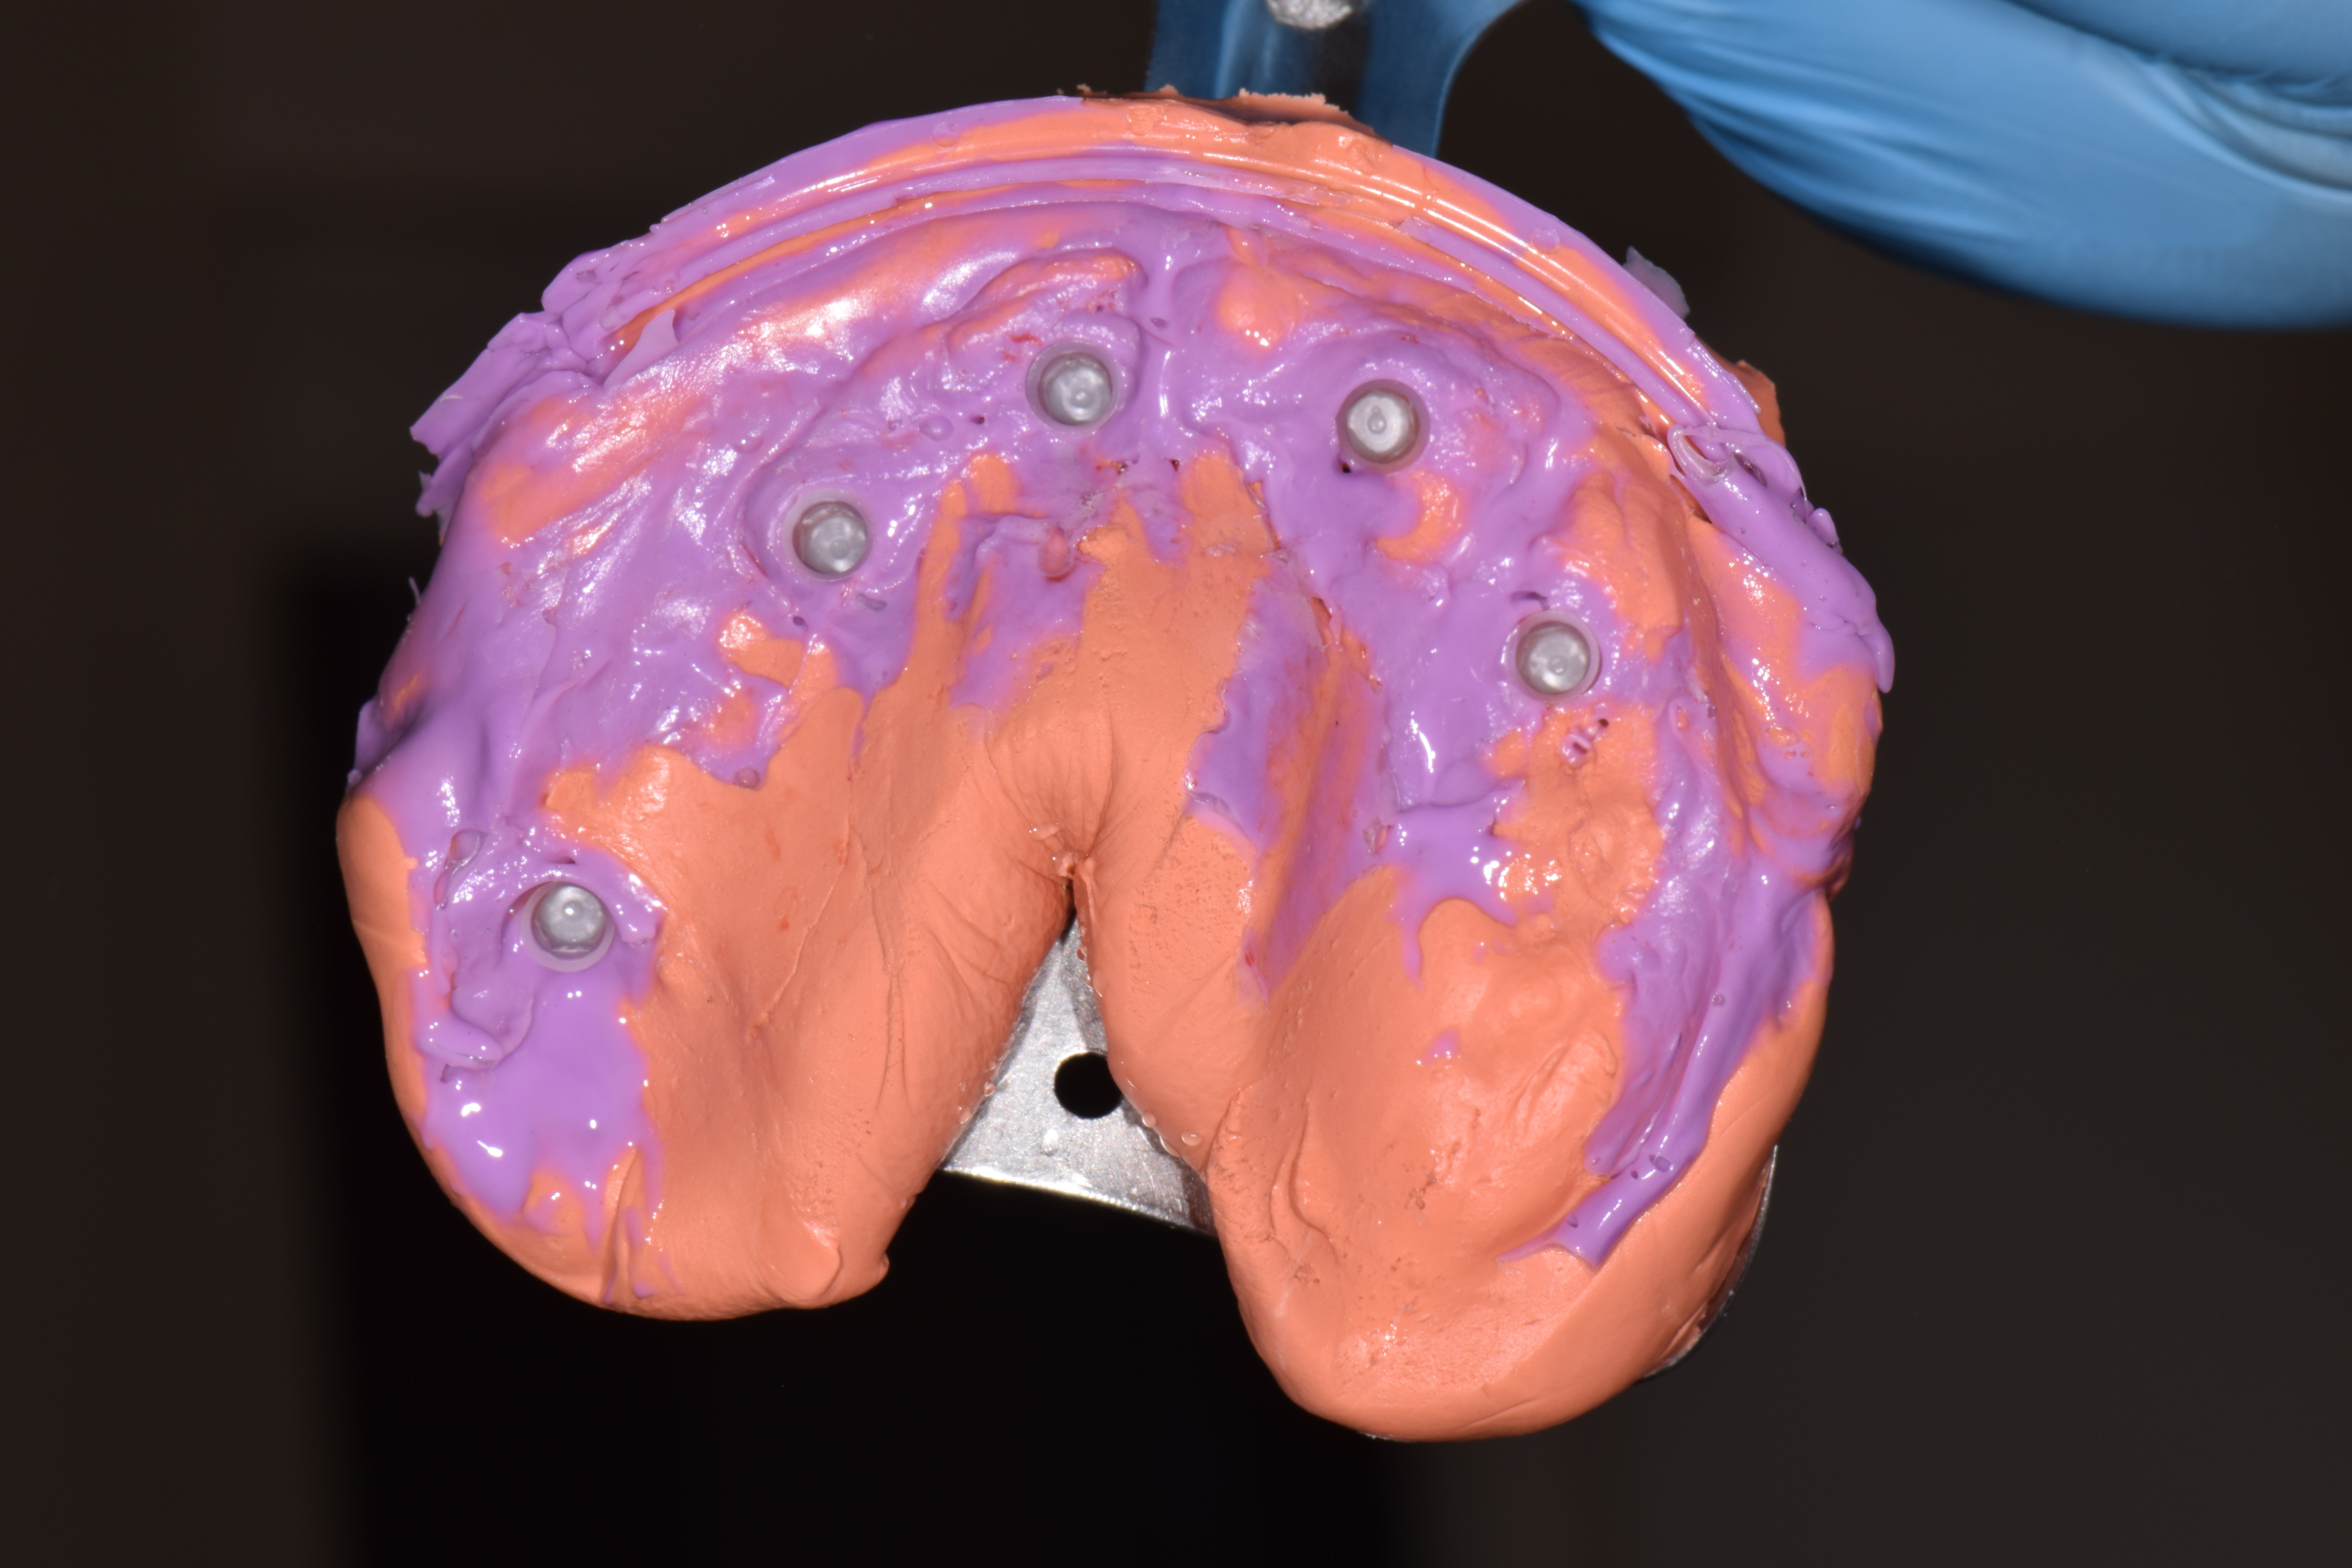

| ИМПЛАНТАЦИЯ |

|

|

|

|

|

|